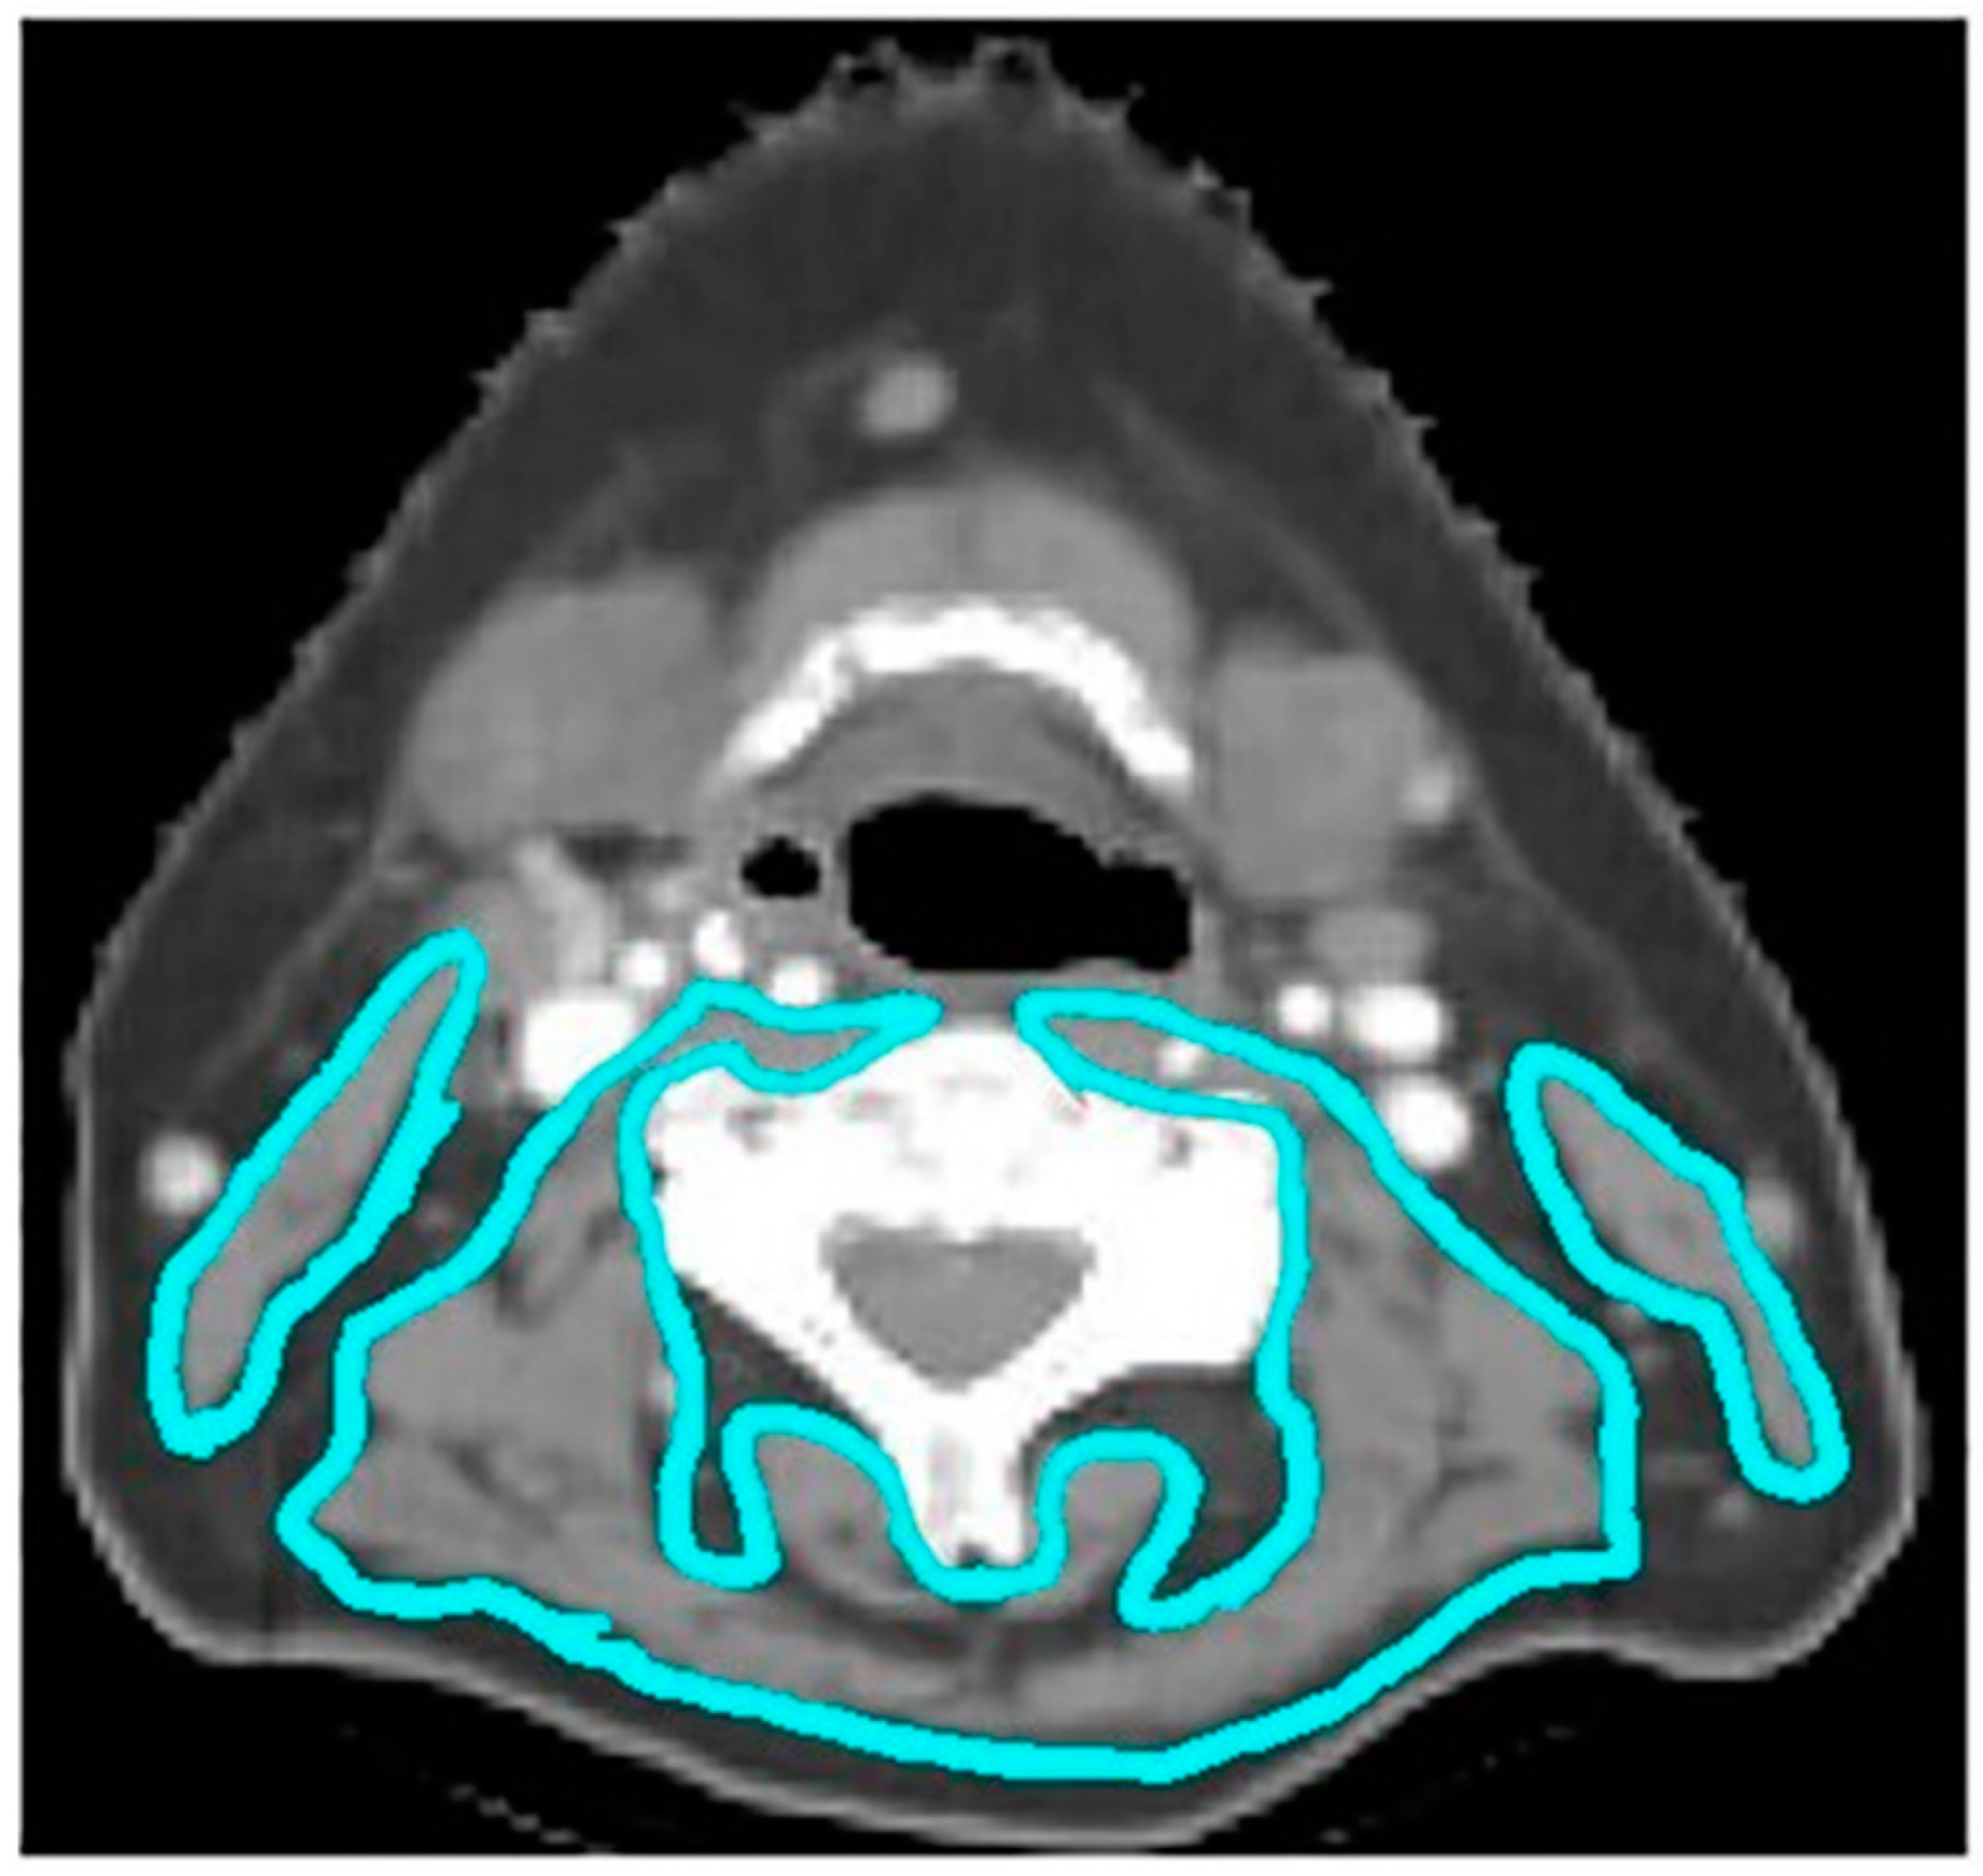

Computed tomography (CT) scans were obtained for all patients at the time of radiation simulation for treatment planning purposes. Body Mass Index (BMI) was calculated using the patient’s weight in kilograms divided by their height in meters squared. Muscle composition was assessed using three different skeletal muscle measures: skeletal muscle index (SMI), skeletal muscle density (SMD), and skeletal muscle gauge (SMG). Skeletal muscle measurements were obtained from treatment planning CT scans using National Institutes of Health (NIH) ImageJ software. All skeletal muscle contouring was performed by a single researcher who was not aware of patient outcomes (R.G.G). An example from this dataset is shown in Figure 1.

Figure 1. A representative case example of a 54-year-old man with an HPV-positive oropharynx cancer. A single axial CT slice is taken at the C3 vertebral body level with contours of the sternocleidomastoid and paravertebral muscles delineated in turquoise. Skeletal muscle was defined as −29 to +150 Hounsfield Units (HUs), and the total cross-sectional area (CSA) was computed automatically within the contoured perimeters.

The presence of sarcopenia was assessed using SMI, a validated method using CT-based measurements to calculate skeletal muscle mass [18,19]. SMI was calculated as previously described by Swartz et al. using a single axial CT slice at the C3 vertebral body level [19]. SMD was calculated using the mean attenuation within the same contoured perimeter. SMI and SMD thresholds were made consistent with thresholds that have been associated with increased mortality in a large cohort of cancer patients [20]. SMG was calculated as the product of SMI and SMD as described by Weinberg et al. [21]. Patients were dichotomized around the median in the overall cohort into low and high SMG groups for data analysis.